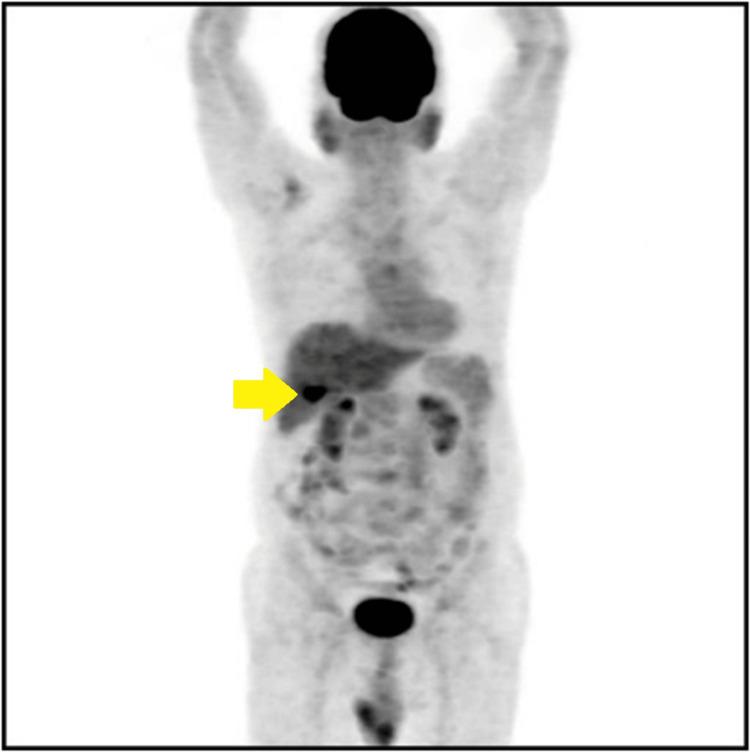

Malakoplakia, a rare granulomatous inflammatory condition, typically manifests in the genitourinary system. Its occurrence in the gallbladder is exceptionally uncommon, posing significant diagnostic challenges. A 68-year-old male presented with recurrent epigastric pain, and a suspicious gallbladder mass was found on imaging. He then underwent surgery due to concerns for malignancy. Histopathology of the surgical specimen revealed malakoplakia, highlighting the diagnostic dilemma encountered in such instances.

软斑病是一种罕见的肉芽肿性炎症性疾病,通常表现在泌尿生殖系统。其在胆囊中的发生极为罕见,带来了重大的诊断挑战。一名68岁男性因反复上腹部疼痛就诊,影像学检查发现胆囊有可疑肿块。由于担心是恶性肿瘤,他随后接受了手术。手术标本的组织病理学检查显示为软斑病,凸显了此类病例中遇到的诊断困境。